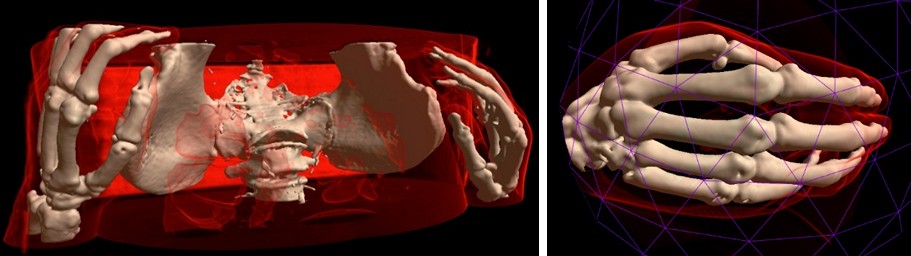

Semi-automatic Methods for Opening Areas of Interest¶

MRI Viewer has two methods for opening/selection areas of interest. The first one allows to clear volumetric data, which obstructs area of interest.

The second method allows to cut the area of interest from the source volume using deformable 3D triangle mesh.